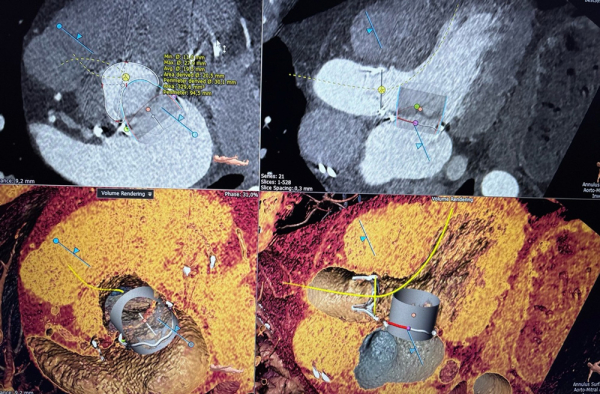

Une analyse multimodale a été réalisée :

- ETO pour évaluer la longueur du feuillet antérieur.

- Scanner cardiaque avec modélisation 3D pour estimer la surface du néo-LVOT,

Le risque d’obstruction est jugé important en raison de la longueur du feuillet antérieur.

Indications principales : TMVI à haut risque d’obstruction :

- Neo-LVOT < 200 mm²

- Feuillet antérieur long / redondant > 24 mm